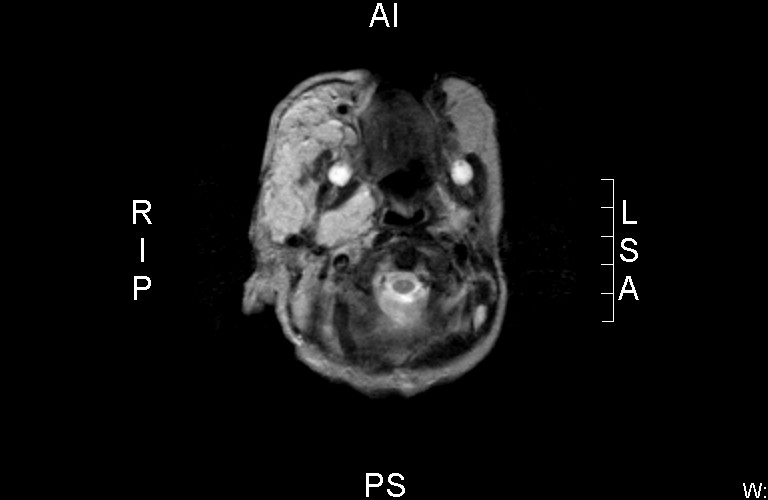

![Dandy-Walker malformatie (click on photo to enlarge) [source: www.huidziekten.nl] Dandy-Walker malformatie](../../../images/Dandy-Walker-malformatie-1z.jpg) |

Dandy-Walker malformatie |

MRI:

Beeld van hemangioom

in de cutis rechts parietaal en frontaal, doorlopend in de rechter orbita.

Hypoplasie van de vermis en de rechter cerebellum hemisfeer met wat wijde

achterste schedelgroeve, gevuld met liquor - beeld passend bij een

Dandy-Walker malformatie.